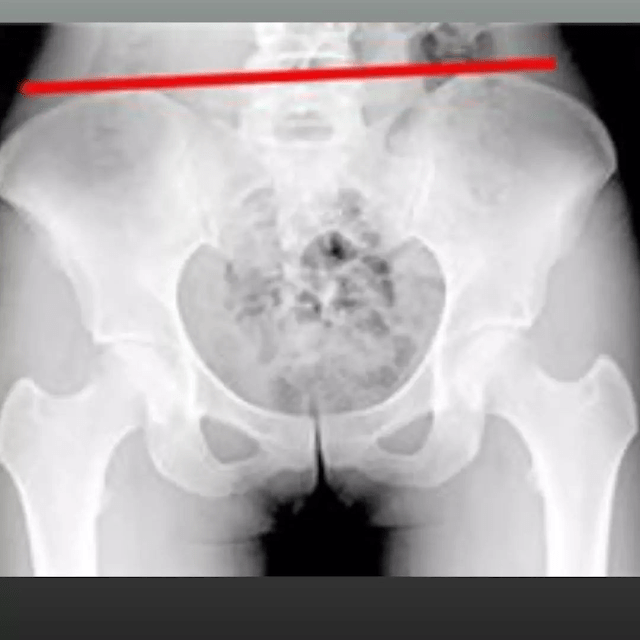

Bacino storto

Va da sé che un bacino disallineato può portare ad un lavoro muscolare errato che, da una parte, indebolisce la muscolatura (di un lato) e, dall’altra, genera un muscolo ipertrofico (al lato opposto del corpo). Quando le ossa non sono allineate, l’integrità articolare, muscolare e perfino emotiva è compromessa.